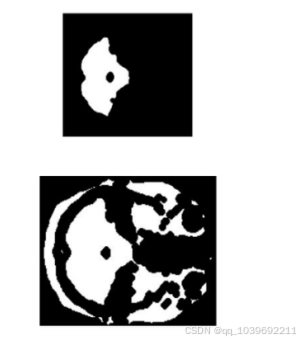

经过迭代式阈值分割法处理后,MRI图像中的鸽脑部分已经趋于清晰,人眼可见呈现一团连通部分。本文采用连

通域标记法,采用MATLAB软件中的算法,提取图像中最大或最小部分,经过一次或多次操作,将图中的鸽脑部分提

取出来。MATLAB程序运行后,输出结果如图3-6所示。

图3-6(a) 形态学腐蚀处理后的图像 图3-6(b)迭代式阈值分割的图像

3.2.5 图像膨胀算法

采用膨胀算法对图像中的小孔和图像边缘的小凹陷进行填充。最大限度地还原鸽脑的原始图像。[22]

腐蚀和膨胀是对偶性的操作。膨胀是将与物体接触的所有背景点合并到物体中,并将边界向外扩展的过程。

[23]通过膨胀,可以填充图像中的小孔和图像边缘的小的凹陷部分。[24]结构元素B对图像A的膨胀,记作